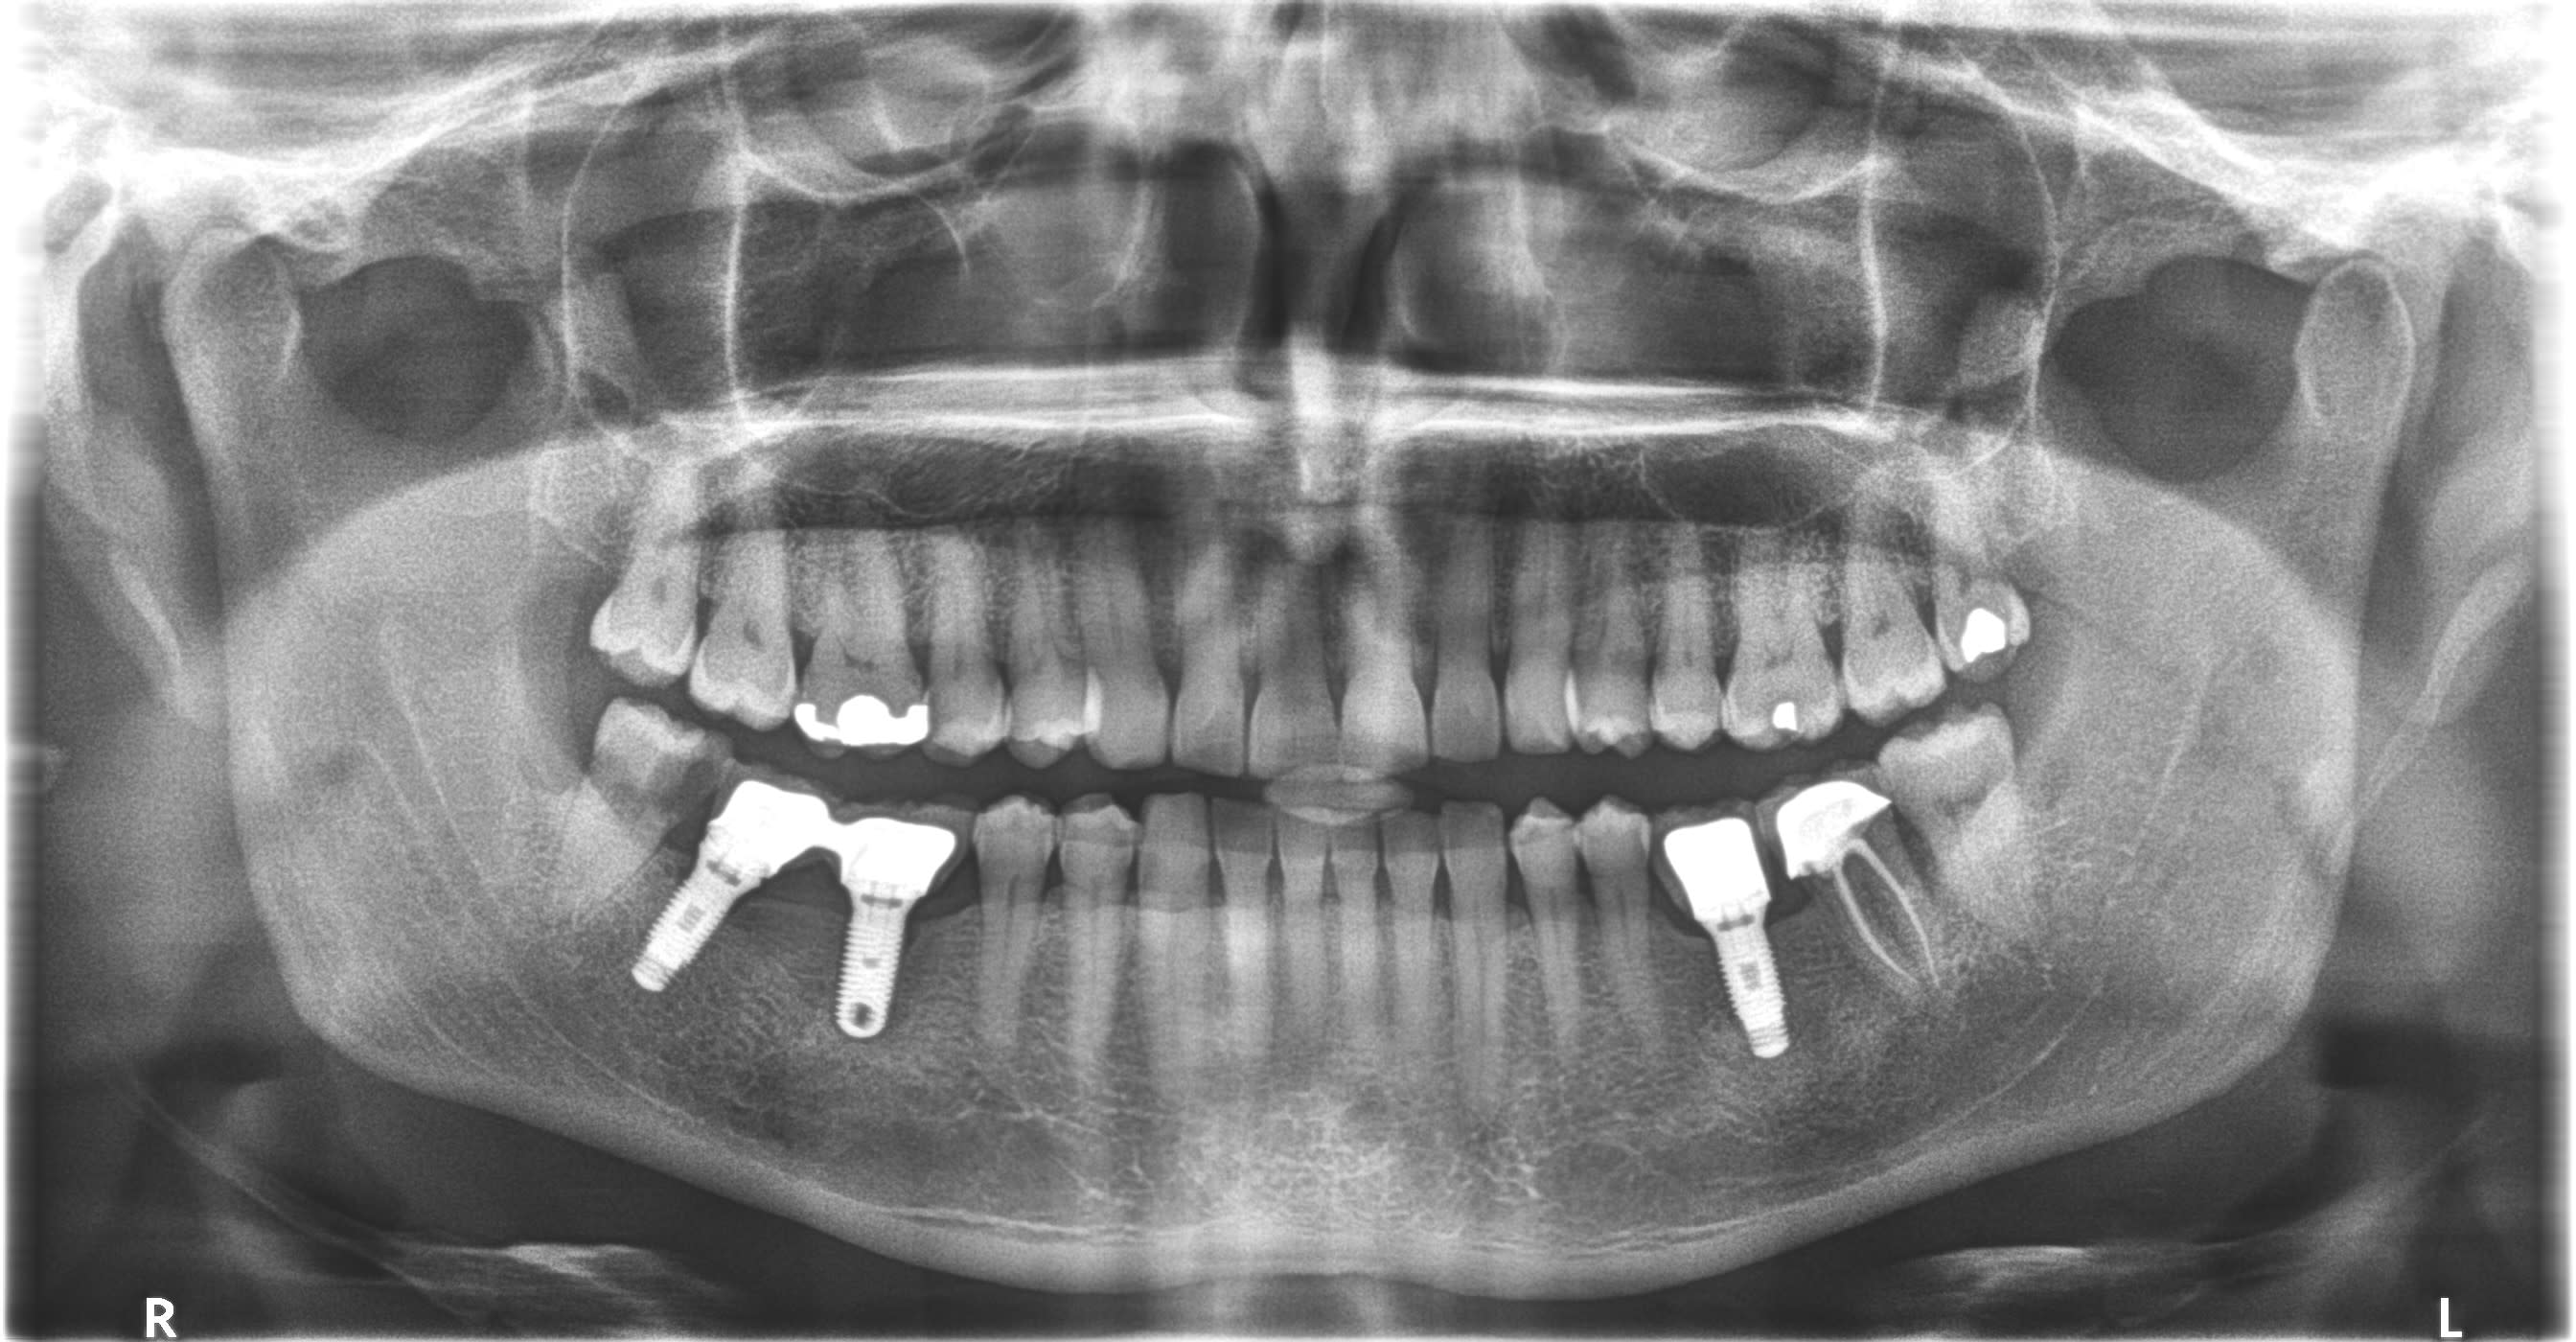

IMPLANT EN 36?

Je pense que les trois sont les mêmes, posés en France en un temps.

ZIMMER TSVM?

Alors zimmer, oui, 100%

Mais pour le coup je pencherais pour des advent car l’évasement au col et la hauteur du filetage de la connexion et de la vis me font plus penser à cet implant tissue level qu’au classique TSV qui lui est un bone level